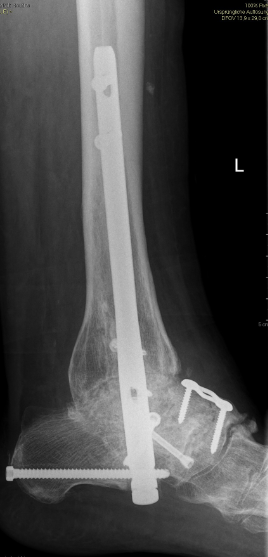

Gesamtes Spektrum der Fuß und Sprunggelenkchirurgie (Plattfuß, Spreizfuß, komplexe Vor-, Mittel- und Rückfußkorrektur, Krallenzehen und Hallux valgus/rigidus, Morton Neurinom)

Chronische und akute Achillessehnenproblematik